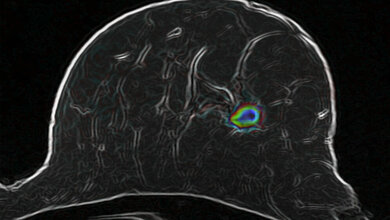

Im Rahmen ihrer Doktorarbeit führte Emily Saunders Protokollbiopsien bei Lebertransplantationspatienten mit normalen Leberwerten ab einem Jahr nach Transplantation durch. Insgesamt konnten 211 Patienten untersucht werden. Nur etwa ein Drittel der Protokollbiopsien waren unauffällig. Über 60 Prozent der Proben zeigten Schädigungen der Transplantatleber, wie Vernarbungen des Gewebes oder Entzündungen. „Diese Schädigungen hätten wir anhand der Laborwerte und dem klinischen Zustand der Patienten nicht erkennen können, sodass eine Steuerung der Immunsuppression nach Lebertransplantation ohne Biopsien ein Blindflug ist“, sagt Dr. Elmar Jäckel, ebenfalls Oberarzt in der Klinik für Gastroenterologie, Hepatologie und Endokrinologie, der das Programm gemeinsam mit Dr. Taubert koordiniert.